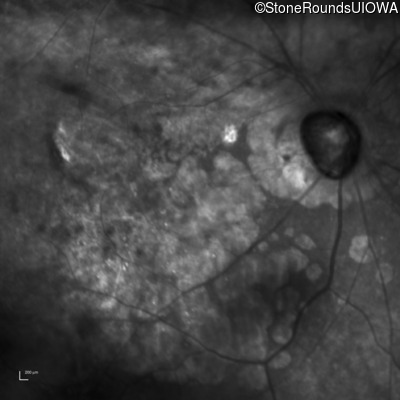

This 81 year old man began using a flashlight to read menus in his 40's. At age 75 his ophthalmologist noticed abnormal fundus findings and referred him to a retina specialist.

| Age at visit: 81 years |

| Age at visit: 82 years |

| Age at visit: 83 years |

| Age at visit: 84 years |

| Age at visit: 85+ (Visit 1) |

| Age at visit: 85+ (Visit 2) |